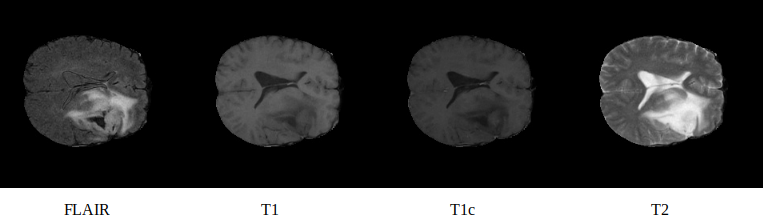

BraTS has always been focusing on the evaluation of state-of-the-art methods for the segmentation of brain tumors in multimodal magnetic resonance imaging (MRI) scans. BraTS 2018 utilizes multi-institutional pre- operative MRI scans and focuses on the segmentation of intrinsically heterogeneous (in appearance, shape, and histology) brain tumors, namely gliomas. Furthemore, to pinpoint the clinical relevance of this segmentation task, BraTS’18 also focuses on the prediction of patient overall survival, via integrative analyses of radiomic features and machine learning algorithms.

Image Shape: 240(Slide Width) × 240(Slide Height) × 155(Number of Slide) × 4(Multi-mode)

Image Mode: 4 (Multi-mode)

channel 0 channel 1 channel 2 channel 3

Label Shape: channel 0: background

channel 1: necrotic and non-enhancing tumor

channel 2: edema

channel 3: enhancing tumor